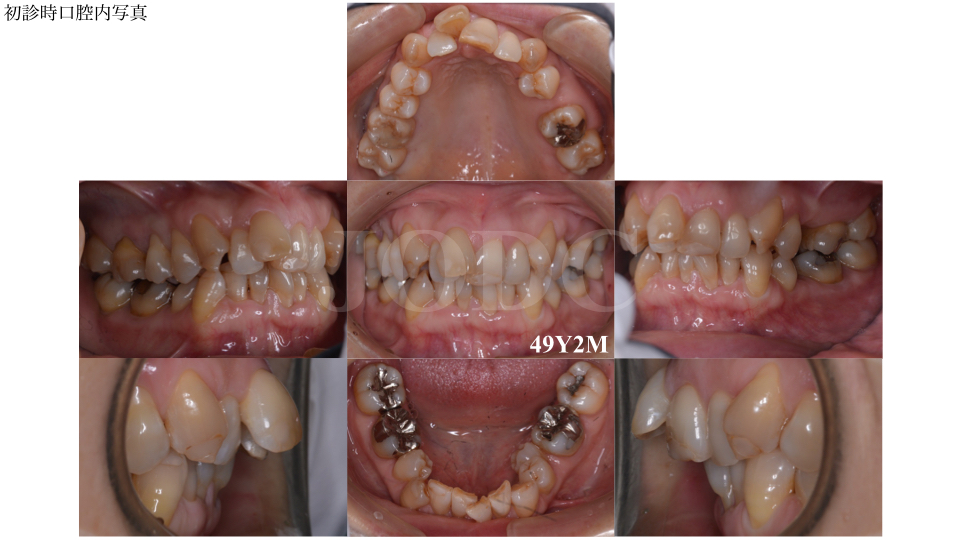

40代 女性 マルチブラケット 非抜歯症例 デコボコ 17年06月30日 12 *患者さんご本人の同意を得た写真を使用しております。 なお、患者さんの状態はお一人お一人異なり、治療内容によっても治療結果は異なります。 主訴 : 歯並びを治したい 初診時年齢: 44歳、女性 診断名: 叢生 治療前: 上あご狭窄歯列を伴う叢生症例です。 40代になって矯正をしているという事実を周りに知られたくない 食事の時にワイヤーに食べ物が詰まってしまうのがたえられなさそう ワイヤー矯正だと歯磨きをするのが大変そう 1日に数度外す時間があるマウスピース矯正のほうがほっとしそう 矯正前、 40代で歯列矯正することに対して、 ネガティブな意見を、よく耳にしました。 その多くが、 40代の矯正は、失敗しやすいからやめた方がいい というものでした。 では、実際に40代で歯列矯正をはじめた、 ぼくの場合はどうだったのか?

40代 女性 マルチブラケット 非抜歯症例 デコボコ 院長ブログ 症例集 ワダ矯正歯科